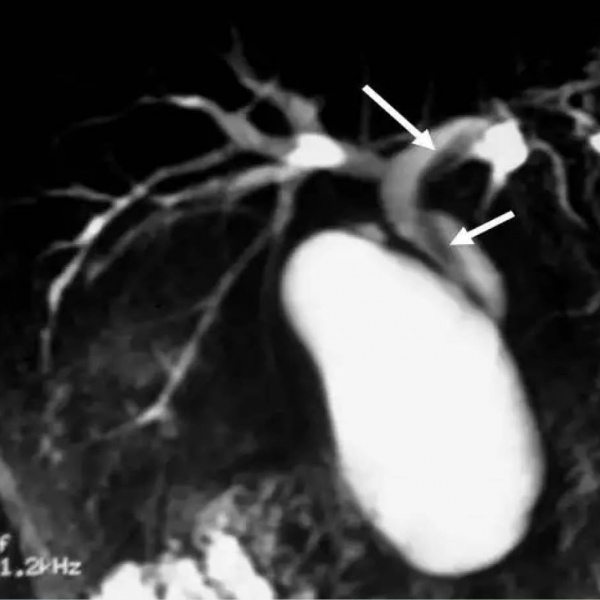

Colangiorresonancia.EN. Codigo 883434 (2022)